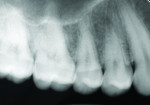

Accurate diagnosis of smooth-surface proximal enamel and dentin carious lesions is highly challenging to the clinician. Interproximal caries is typically diagnosed using an intraoral clinical assessment, including visualization of superficial enamel discolorations combined with using an explorer to feel for surface roughness and cavitation combined with the use of bitewing radiographs.8-11 In most clinical cases, the access to evaluate the posterior proximal site visually and tactilely is very limited. Radiographs are an important diagnostic tool for the detection of interproximal caries,12,13 and bitewing radiographs are the most frequently used aid in assessing the potential for caries on the proximal tooth surface. Yet, the detection of interproximal caries using bitewing radiographs has been demonstrated to have an accuracy estimated at 40% to 65%.14-16 Also, there is significant variation among clinicians regarding how often diagnostic radiographs should be taken.17 As health professionals, dentists are concerned about limiting their patients’ ionizing radiation exposure. It is well accepted and proven that ionizing radiation dosages are cumulative in their effects and their risks.18,19

To visualize posterior proximal caries using a conventional light guide, the probe is placed on the cervical area of the tooth, buccally or lingually. Light passes into the cervical tooth structure and then radiates occlusally. Caries can appear as a dark shadow on the occlusal surface (Figure 2).